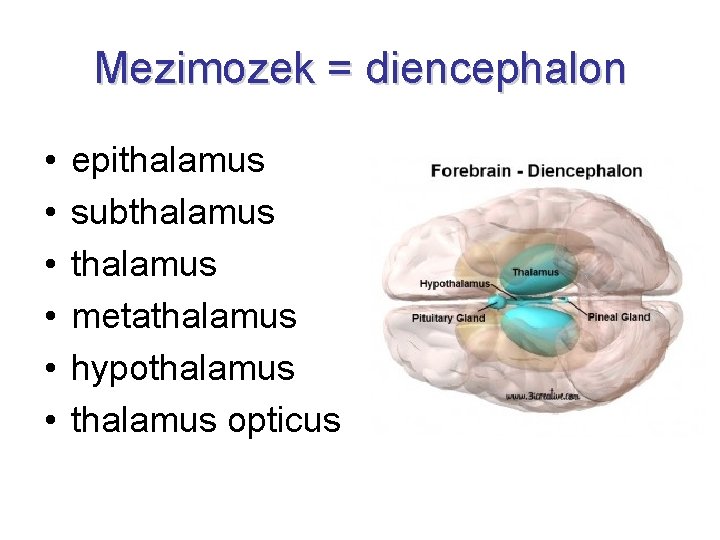

Mezimozek = diencephalon • • • epithalamus subthalamus metathalamus hypothalamus opticus

Mezimozek - vývoj alární ploténka → thalamus, subthalamus bazální ploténka → hypothalamus canalis centralis → 3. komora fissura telodiencephalica sulcus hypothalamicus